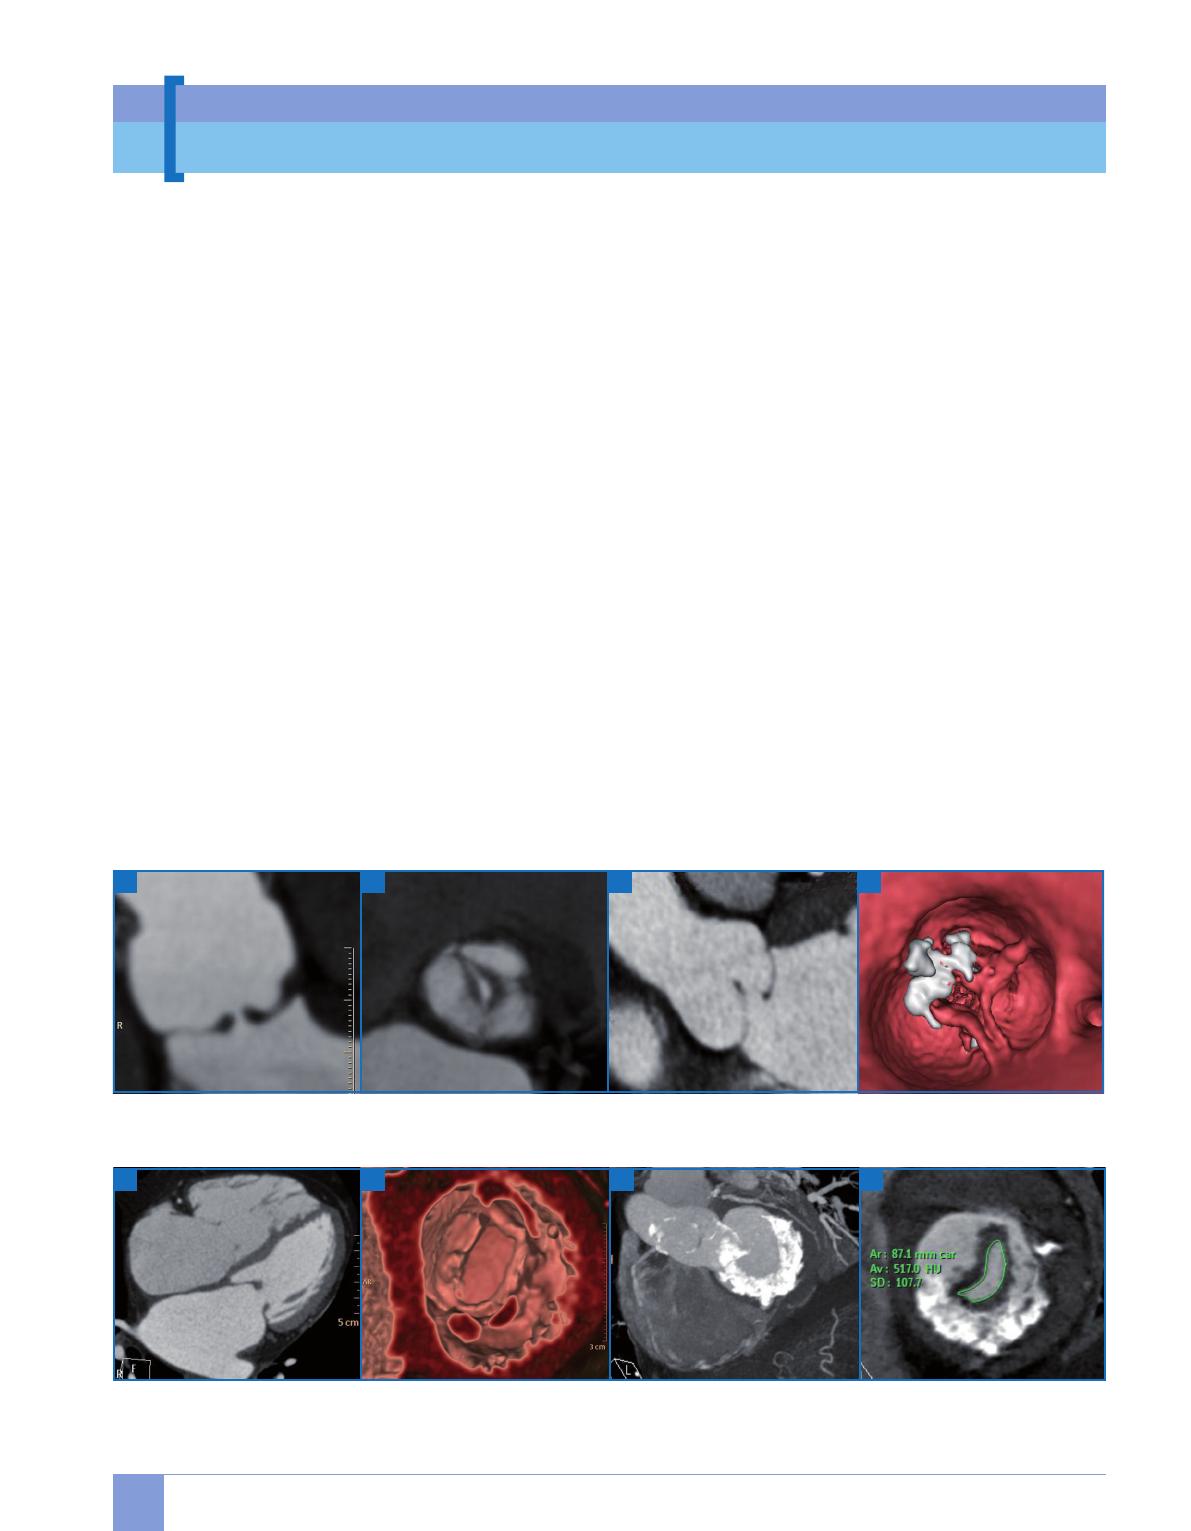

[ Prothèses (fig. 8 et 9)

Contrairement aux ultrasons, les valves

prothétiques mécaniques en carbone se

prêtent elles-mêmes particulièrement

bien à l’étude tomodensitométrique en

raison de leur fort contraste spontané avec

les tissus mous et le sang opacifié, permet-

tant notamment un radiocinéma de valve

en 3D avec mesure fiable des angles d’ou-

verture et de fermeture, voire le diagnostic

rétrospectif de mismatch par la mesure

directe de la surface anatomique de la

prothèse. Par contre, la forte différence de

densité est à l’origine d’artefacts de bloo-

ming et de durcissement, d’intensité et de

localisation variables, plus marquées pour

les valves métalliques et certaines valves

à disque, pouvant perturber la lecture des

tissus adjacents. La thrombose est visuali-

sée sous la forme d’une image de densité

tissulaire adhérente à la prothèse quelle

que soit son site, quand l’ETO 3D est plus

performante sur le versant auriculaire

d’une prothèse mitrale et plus aléatoire

sur une prothèse aortique.

La désinsertion de prothèse est visua-

lisée par le défect tissulaire péripro-

thétique, permettant une localisation

topographique précise, notamment

par rapport aux ailettes, avec mesure

des dimensions et étude des structures

environnantes, participant à la décision

d’une tentative de fermeture percuta-

née, voire son contrôle post-procédure.

La visualisation d’un pannus en scanner

est très bien corrélée avec les constata-

tions peropératoires et permet de le dif-

férencier d’une thrombose dans les cas

d’élévation de gradient [10, 11].

Concernant les bioprothèses, la sémio-

logie est hybride entre prothèses méca-

niques et valves natives. La dégénéres-

cence calcifiante est particulièrement